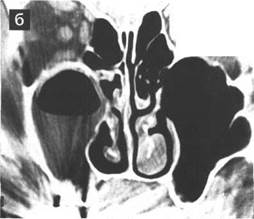

них и задних решетчатых артерии, горизонтальная часть ситовидной пластин­ки, а также боковая стенка клиновидной пазухи и задних решетчатых клеток, в которую могут вдаваться костные каналы зрительных нервов и сонных арте­рий. Для изучения области ситовидной пластинки мы проводили исследова­ние в коронарной проекции. Область ситовидной пластинки имеет форму сту­пеньки, высота которой может значительно варьировать в зависимости от ин­дивидуальных особенностей. Наиболее опасны в плане повреждения мозго­вых оболочек с последующей ликвореей случаи, когда ситовидная пластинка находится на 4-6 мм ниже, чем крыша решетчатого лабиринта (рис. 12). Сре­ди обследованных нами 225 пациентов с хроническими синуситами низкое и не симметричное (справа и слева) распо­ложение ситовидной пластинки по отно­шению к крыше решетчатого лабиринта отмечено у 8 человек (3, 5%). Коронарная проекция позволяет уточнить ширину ре­шетчатой воронки (инфундибулум), то есть расстояние между крючковидным от­ростком и медиальной стенкой глазницы. В случаях, когда крючковидный отросток располагается вплотную к орбитальной стенке, существует опасность ее пенетра-ции иглой или серповидным скальпелем уже в самом начале операции - при вы­полнении инфильтрационной анестезии и резекции крючковидного отростка.

Рис. 12. КТ ОНП, коронарная проек­ция: а) асимметрия расположения ситовидных пластинок - левая нахо­дится ниже правой (стрелка); 6) асимметрия в строении крыши решетчатого лабиринта: справа кры­ша решетчатого лабиринта располо­жена выше, чем слева (стрелка).